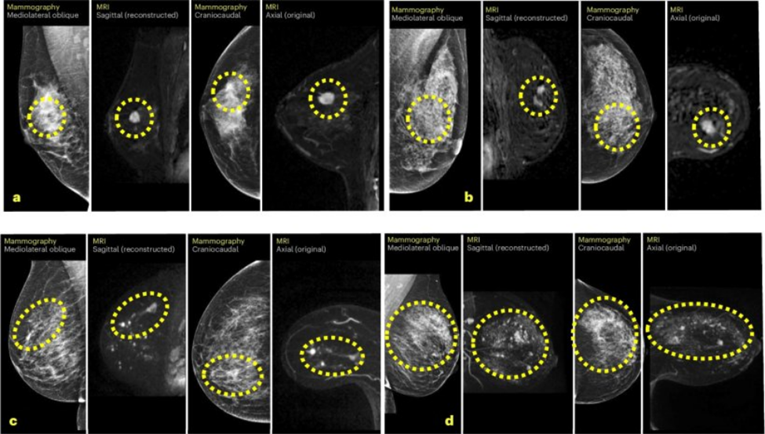

Koristeći Mirai, algoritam umjetne inteligencije utemeljen na dubokom učenju, grani strojnog učenja posebno prikladnom za rješavanje problema iz područja umjetne inteligencije, istraživači su proučili svaki mamogram da bi generirali personalizirani trogodišnji rezultat rizika na temelju gustoće dojki i suptilnih značajki snimanja nevidljivih ljudskom oku.

"Naši nalazi upućuju na to da bi pregled najrizičnijih 20 posto mamograma koje je označila umjetna inteligencija mogao pridonijeti ranijem otkrivanju gotovo polovice intervalnih karcinoma", rekao je voditelj istraživanja, prof. Joshua W.D. Rothwell. "To bi kliničarima moglo omogućiti da pacijenticama s najvećim rizikom ponude i dodatna snimanja, poput magnetske rezonancije ili mamografije s kontrastom."

Prediktivna točnost alata bila je najjača unutar prve godine nakon screeninga, što ovaj alat čini vrijednim pomagalom u poboljšanju učestalosti probira i strategija praćenja. Premda je model umjetne inteligencije bio nešto manje učinkovit u žena s iznimno gustim tkivom dojke, ipak je premašio tradicionalne metode procjene rizika.

Razvijen na Medicinskom fakultetu Sveučilišta Washington i po licenci tvrtke Prognosia Inc., softver koristi 2D i 3D mamografske slike za izračun petogodišnjeg rizika od raka dojke za svaku pojedinu pacijenticu, oslanjajući se isključivo na podatke dobivene snimanjem i na životnu dob.

S obzirom na desetke tisuća arhiviranih mamograma iz Centra za rak Siteman u koje je imala uvid, umjetna inteligencija uspijeva otkriti suptilne abnormalnosti nevidljive ljudskome oku i predviđa rizik od razvoja raka s više od dvostruke točnosti u odnosu na tradicionalne metode.